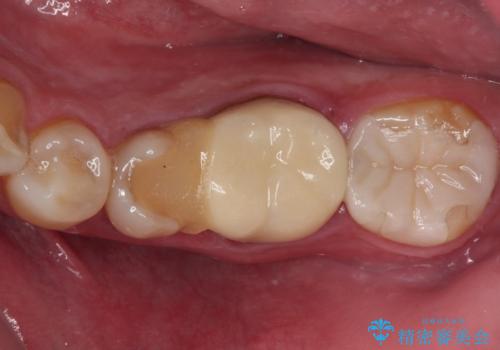

根管治療の際に、咬み合う上顎の銀歯が内側に入り込んでいることも気になるとのことであったため、部分矯正を行い、その後上下を同時に補綴治療することとしました。

部分矯正を行うと咬み合わせが定まらないことがありますが、今回は矯正治療後に上下補綴治療を行ったため、安定した咬み合わせにて仕上げることができました。